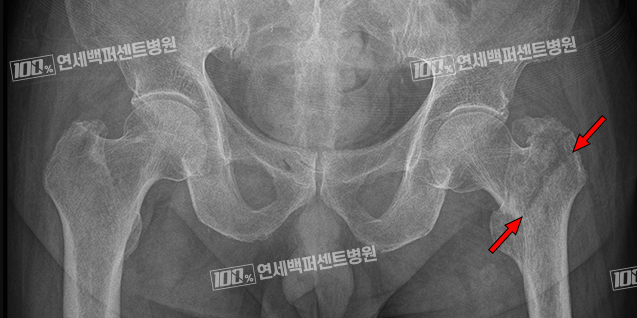

고관절 골절 정복 및 내고정술

전자간 골절, 전위가 없는 급성 대퇴경부골절의 경우에는 골절 부위를 나사와 금속판 또는 골수정을 이용하여 고정하는 수술을 합니다.

부러진 뼈가 완전히 붙기까지는 보통 2~3개월 정도 소요되며 뼈가 완전히 붙을 때까지 과도한 운동을 삼가하고 안정을 취해야 합니다.

대퇴골 전자간 골절 수술 전

대퇴 골수정 고정술 후

전위없는 급성 대퇴경부 골절 수술전

다발성 금속 나사 고정술 후